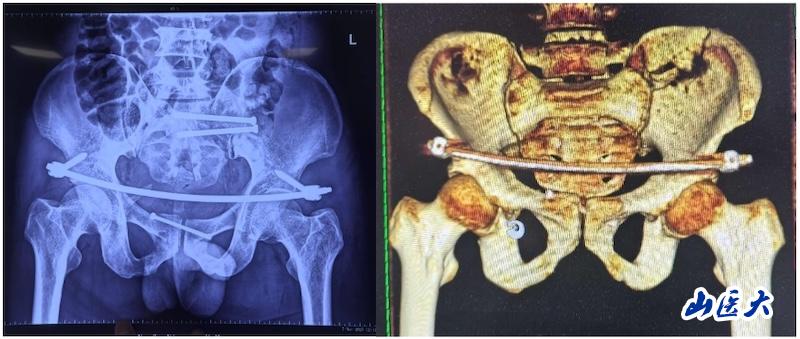

医疗技术新飞跃——我校第二医院骨科采用UCRT解锁复位及机器人技术成功救治骨盆骨折患者

近日,我校第二医院骨科成功为一位骨盆骨折患者实施了UCRT解锁复位术,术中,医务人员结合先进的O-arm术中影像系统和天玑机器人技术,实现了微创治疗骨盆骨折的新突破。

该患者在驾驶三轮车时发生车祸,导致骨盆骨折,经过当地医院对症治疗后转入我校第二医院急诊科。由于血色素持续下降,血管外科首先进行了血管介入栓塞处理,随后转入骨科创伤病区,由孙海钰团队接续治疗。经过详细检查和评估,孙海钰主任、贺冬冬副主任医师、王欢副主任医师为患者制定了运用UCRT解锁复位技术,结合天玑机器人及O-arm术中影像系统为其实施骨盆闭合复位的手术治疗方案。3月6日,孙海钰团队在骨科老一辈专家尹芸生主任的指导及麻醉师、技师、器械护士和巡回护士的通力协助下,成功运用微创新技术为患者实施了手术。

据孙海钰介绍,骨盆髋臼骨折是一种严重的创伤,传统开放复位内固定术创伤大、恢复慢,而闭合复位则具有微创、出血少、恢复快等优点。随着医疗技术的不断进步,UCRT解锁复位技术结合天玑机器人及O-arm术中影像系统为骨盆骨折治疗提供了更加精准、微创的解决方案,该技术代表了当前骨盆骨折治疗的前沿方向。